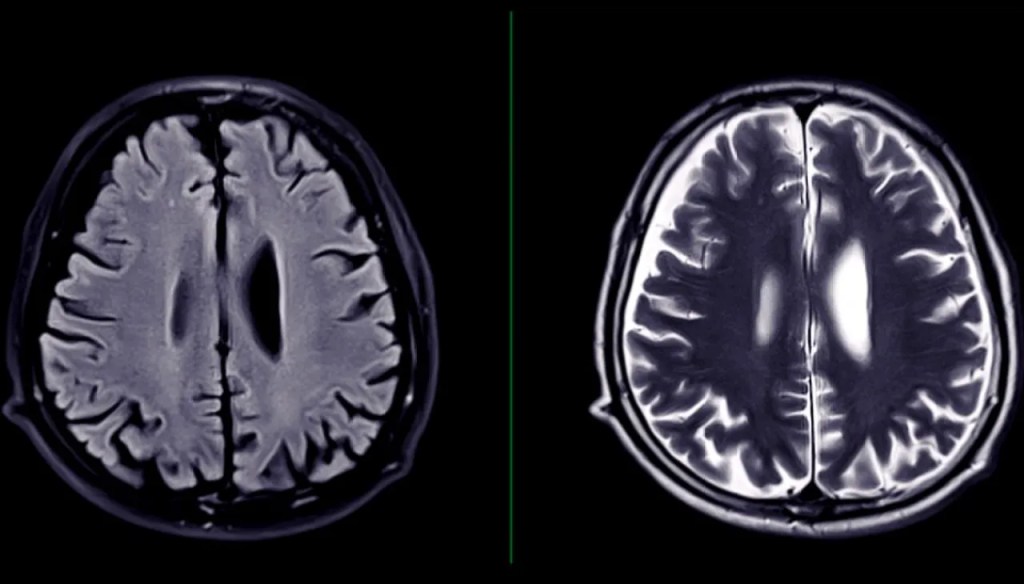

“[It] usually begins in small spots in the frontal lobes,” Dr. Anne McKee, the director of the CTE Center at Boston University, told CBS News. “But over time, with aging, it starts affecting widespread regions of the brain and can cause profound memory loss and even dementia.”

Like many neurodegenerative diseases, CTE can only be definitively diagnosed after death. In some cases, individuals experiencing unexplained mood shifts, paranoia or psychological distress have expressed concern over their brain health before taking drastic action—including requesting post-mortem analysis. While troubling, these instances highlight the urgent need for earlier detection and intervention.

As of publication, there is no cure for CTE, but researchers are actively working on creating one. They are also working on figuring out how to diagnose the disease in a living person, since as of now, they can only do it “by examining samples of a person’s brain with a microscope. But they can only do this during an autopsy after someone dies,” per the Cleveland Clinic.